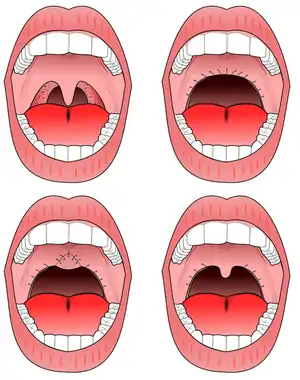

Uvulopalatopharyngoplasty (UPPP)

The procedure most commonly performed for sleep apnea is the uvulopalatopharyngoplasty (UPPP). This involves removal of the tonsils if still present, and a subsequent palatal procedure. The tonsil pillars are often sutured closed—and the uvula is either trimmed, cut, folded, reshaped, or sutured to the soft palate.[9] Studies have shown that treatment effect of UPPP with tonsillectomy increases with tonsil size.[10]

Some procedures attempt to widen the airway by removing tissues in the back of the throat, including the uvula and pharynx. These surgeries are quite invasive, however, and there are risks of adverse side effects. The most dangerous risk is that enough scar tissue could form within the throat as a result of the incisions to make the airway more narrow than it was prior to surgery, diminishing the airspace in the velopharynx. Scarring is an individual trait, so it is difficult for a surgeon to predict how much a person might be predisposed to scarring. Currently, the American Medical Association does not approve of the use of lasers to perform operations on the pharynx or uvula.